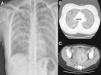

Mujer de 29 años natural de Bolivia que presentaba un cuadro progresivo de febrícula, tos seca y disnea de esfuerzo, refiriendo además en los últimos 3 meses, tras aborto terapéutico, dolor abdominal y leucorrea que no había mejorado pese a antibioterapia dirigida con ciprofloxacino por cultivo de exudado vaginal positivo para Escherichia coli. Se realizaron radiografía y TAC de tórax donde se observaba una afectación micronodulillar extensa bilateral (figs. 1A y B), TAC de abdomen que evidenció imágenes quísticas tubulares parauterinas con edema de grasa periférica y lámina de líquido libre compatibles con salpingitis (fig. 1C), Mantoux que no generó induración alguna y baciloscopia y cultivos en medio de Löwenstein de muestras de esputo y exudado vaginal, en los cuales creció Mycobacterium tuberculosis.